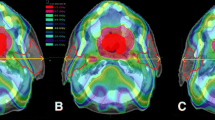

The parotid gland volume significantly reduced by 28.0% during treatment (P < 0.01). The lateral borders of the parotid glands demonstrated a significant medial shift of 1.2 mm (range − 0.1 to 3.4 mm; P = 0.02), however the centres of mass did not shift medially (P = 0.51). The submandibular glands reduced significantly in volume by 26% (P < 0.001). A significant superior shift of the submandibular glands was observed at all fractions except for fractions 20 and 35. At fraction 30, a 2.4 mm superior shift (range − 2.3 to 10.3 mm, P = 0.02) was observed. Although the adapted plans met the parotid gland dose constraints (V26 < 50%), the adapted plan delivered a higher parotid gland dose compared to the original plan (38% vs. 44%, P = 0.001). However, further retrospective replanning (ART2), with optimisation parameters placing more importance on the parotid gland dose, was able to obtain both improved TV coverage and reduced parotid gland dose (Fig. 3).

Although the parotid gland dose remained within acceptable IMRT planning dose constraints (i.e., V26 < 50%), our patients received a higher parotid gland dose with the adaptive plans, compared to the original treatment plan. This occurred because, in order to begin treatment using the adaptive plan within 24 h, the first acceptable adaptive treatment plan meeting the requirements for PTV coverage and the parotid gland dose constraints (V26 < 50%) was utilised. Subsequent retrospective replanning demonstrated that it was possible to create an adaptive plan with improved coverage of both the PTV and the parotids, with little additional planning time. A limitation of our study is that prospective parotid gland sparing was not prioritised sufficiently. This could have been avoided, without slowing the replanning process, by modifying the optimisation criteria for the parotid glands at the time of adaptive replanning.

Coverage of the PTV70 on original plan (left) and adaptive plan (right). CTVp orange, CTVn light orange, PTV70 purple, 95% isodose line green (TIF 1245 KB)

Coverage of the PTV60 on original plan (left) and adaptive plan (right). CTVp orange, CTVn light orange, CTVn0 yellow, PTV60 purple, 95% isodose line green (TIF 1341 KB)